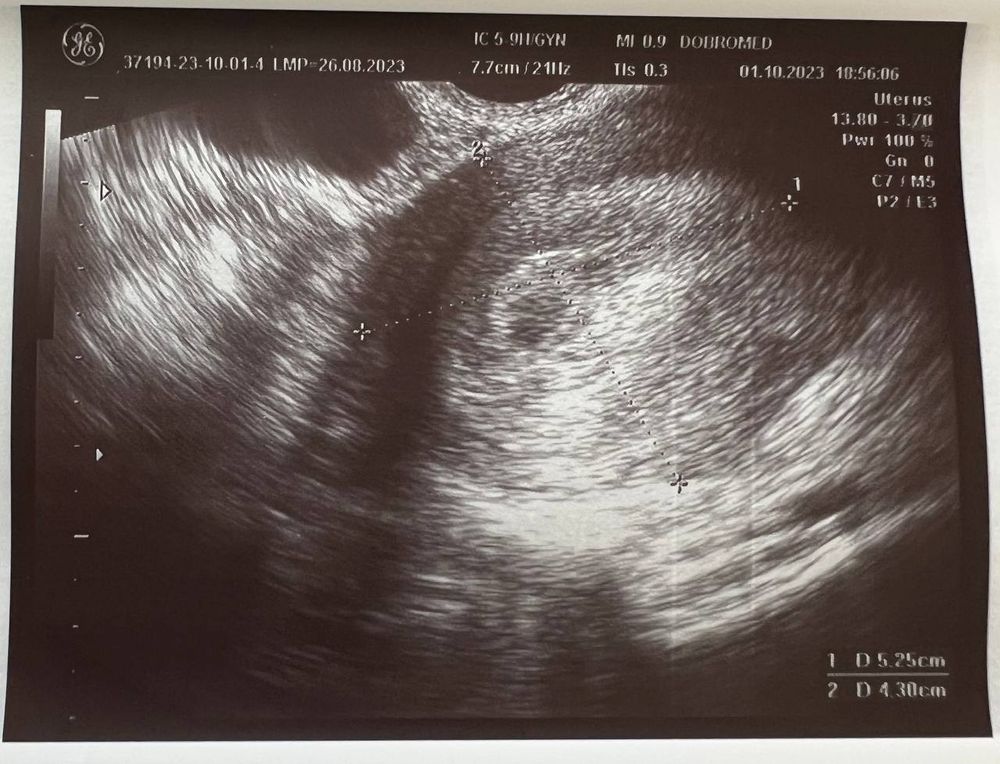

Вчера (1 октября) сходила на УЗИ, беременность подтвердили, маточная.

Размер плодного яйца 4 мм.

Но не видно желтое тело, и мутное содержимое плодного яйца (как она сказала). Меня напугала очень узистка... мол, может быть замершая беременность.

Если есть специалисты тут - пожалуйста, посмотрите снимок

Про мутность в плодном яйце в заключении не сказано. То что нет желточного мешочка, так срок еще маленький, через недельку все должно появиться. Не переживайте. Из тревожного тут только повешенный тонус, и то возможно это реакция на узи датчик. Папаверин повставляйте на ночь до следующего узи. Все должно быть хорошо! 🕊️